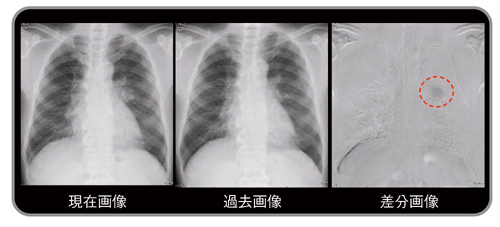

図5 有用症例:境界不鮮明な陰影(小細胞癌)